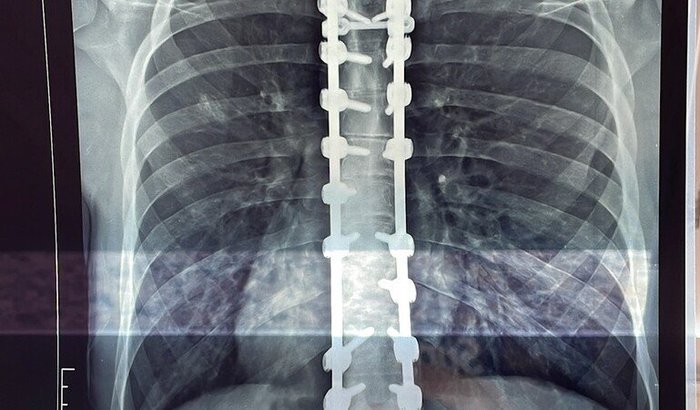

Há 4 anos, precisei passar por uma cirurgia para tratar a Cifose de Scheuermann e a Escoliose. Desde então, fui forçado a viver com a inserção de pinos e hastes na minha coluna. Contudo, devido ao desgaste e a quebra dos implantes, parafusos e pinos ao longo desses 4 anos, além do surgimento de uma infecção bacteriana, preciso de uma nova cirurgia com urgência.

O quadro é grave. Se a infecção não for controlada, pode comprometer minha saúde de forma fatal. Com a cirurgia, será necessário retirar os pinos e hastes, tratar a infecção e corrigir o problema que se agravou ao longo do tempo.